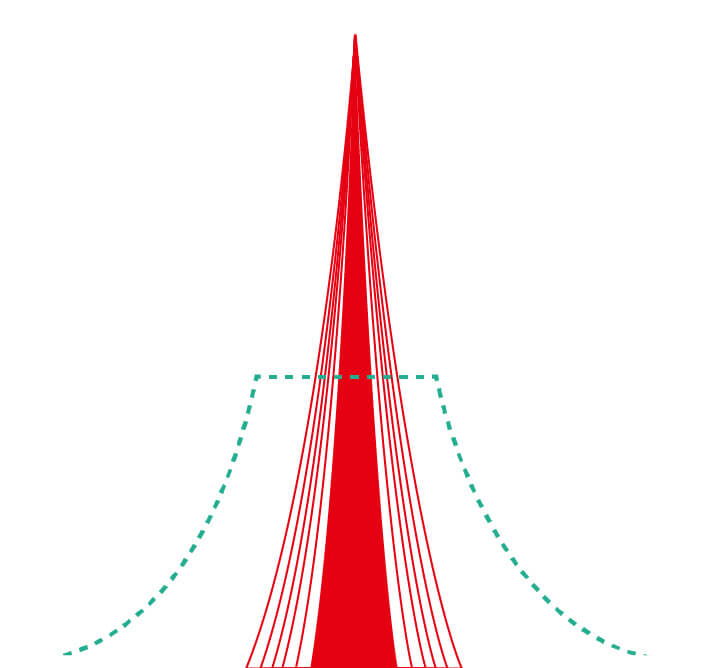

百老汇电子游戏官网新开发的内镜染色技术,主要是基于多波长LED 光源的开发,VLS-55Q 四波长LED 光源是由四个不同颜色的LED光按照相应照明模式所规定的特定发光比例进行合束后形成,合束后形成的照明光的光谱由红光、绿光、蓝光及蓝紫光这四个不同的波段范围构成。具有更高光谱自由度,通过光谱比例的控制,实现了聚谱成像技术,英文全称为“Spectral Focused Imaging, SFI”,缩写为“SFI”和光电复合染色成像技术,英文全称为“Versatile Intelligent Staining Technology, VIST”,缩写为“VIST”。